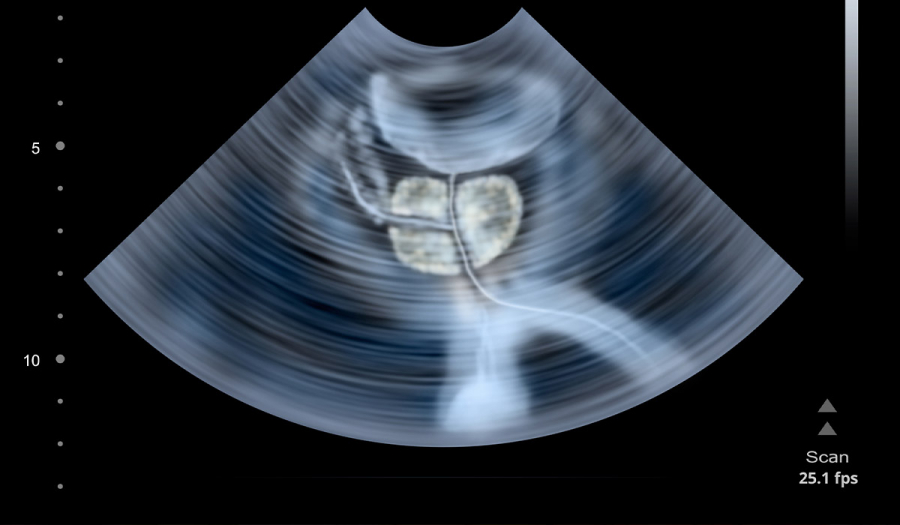

УЗД передміхурової залози – ефективний метод контролю стану даного органу, що дозволяє виявити зміну в його розмірах і стані тканин.

Передміхурова залоза – орган, який розташований біля вершини сечового міхура і являє собою гладком’язову і залозисту структуру. Простата грає дуже важливу екзокринну й ендокринну функцію в тілі чоловіка.